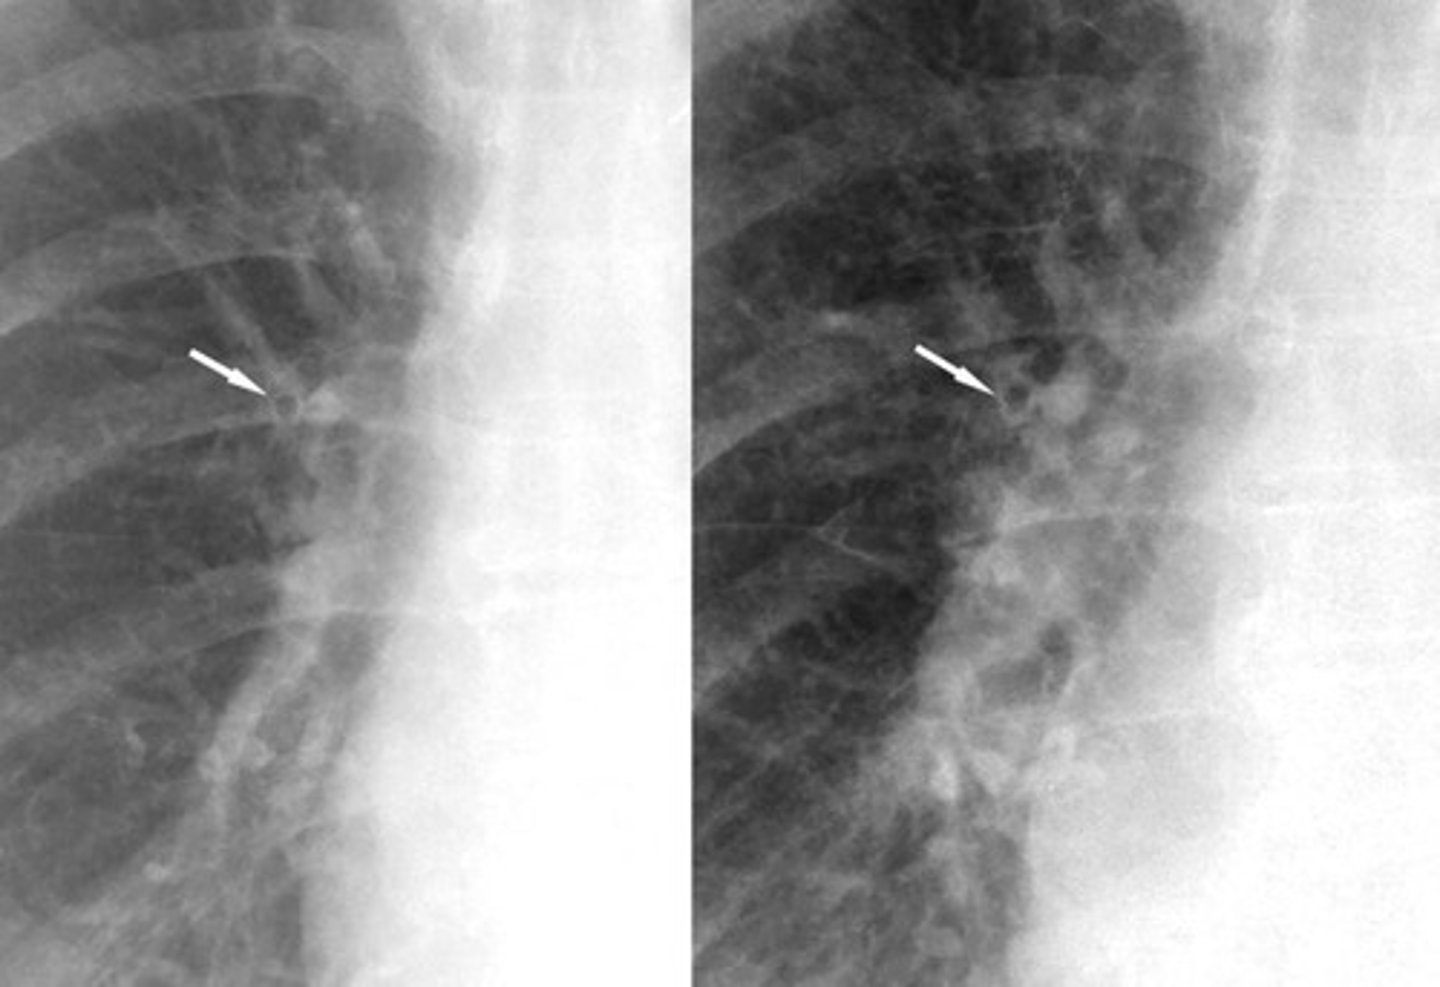

-very small, blister like lesion on visceral pleura normally at apex

-can't be seen on XR, very thin walled

Blebs on an CT

-bigger than 1cm, associated with emphysema

-seen as localized paucity of lung markings

-thin wall (<1mm)

-seen better with CT than XR

Bullae appearance